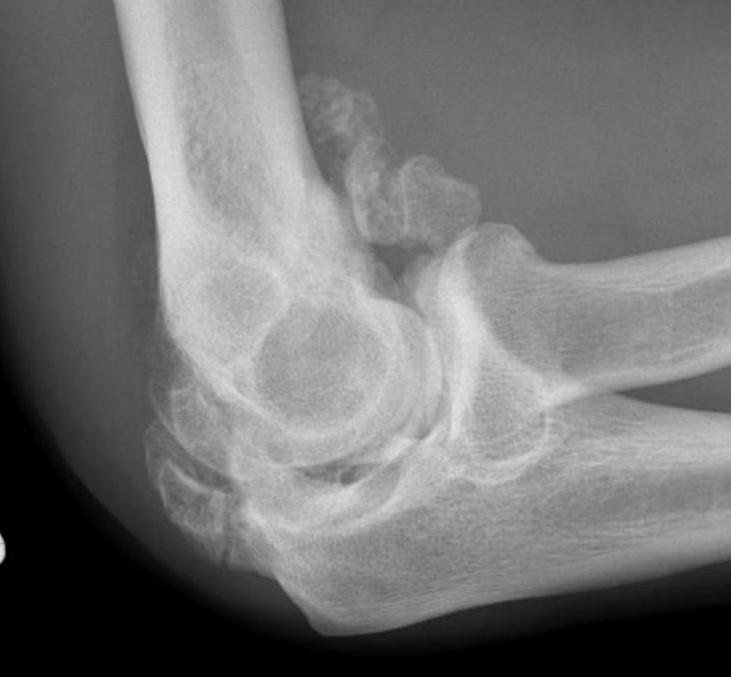

Radio-ulna synostosis

synostosissynostosis

Definition

Fusion between radial and ulna that limits rotation